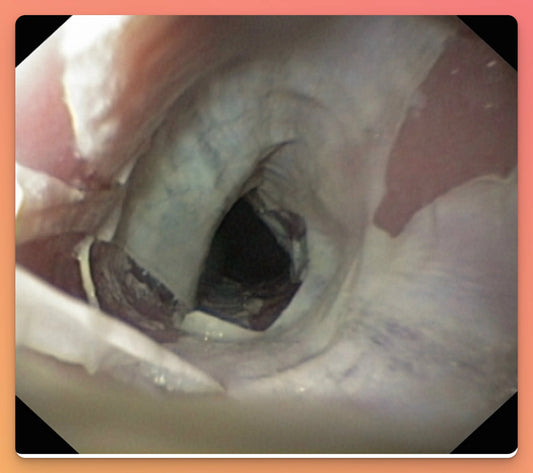

(DIE) - Dabigatran-Induced Exfoliative Esophagitis

Non-vitamin K anticoagulants (NOAC), also known as direct oral anticoagulants (DOAC) are now commonly used for a variety of conditions requiring chronic anticoagulation. The dabigatran pellets are covered with a...